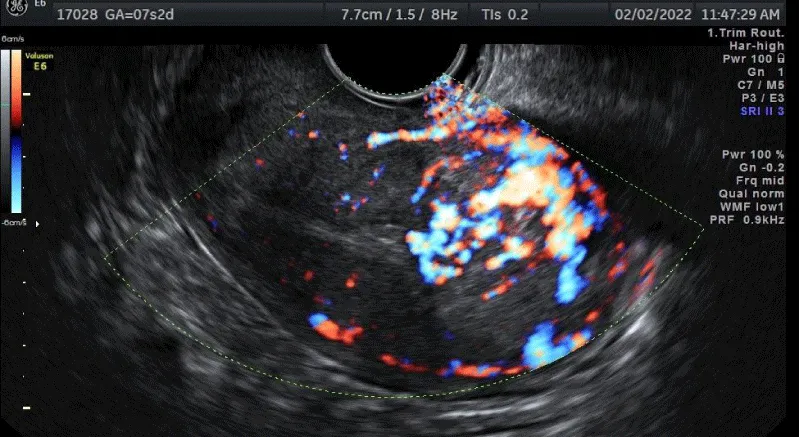

A detailed exam of the pelvis’ US by the expert operator using Voluson E6 (General Electric Healthcare GE, Zipf, Austria) with broadband from 5 - 9 MHz endocavitary transducer was performed with a Color Doppler examination. It showed a retroverted uterus and regular morphology of the external profile measuring 84 mm LL x 55 mm AP x 70 mm TD. Cavity length was 50 mm while cervical length was 22 mm. The right laterofundic portion of myometrium was occupied by a lesion measuring 50 x 44 x 48 mm with an inhomogeneous echostructure of the grey scale. Color Doppler shows that the lesion was richly vascularized (CS4) with rear acoustic reinforcement (Figure 2a,2b). The endometrial line was 9 mm, with homogeneous hyperechogenicity and regular mio-endometrial junction. Ovaries were bilaterally regular, measuring 29 x 15 mm on the right and 31 x 17 mm with corpus luteum on the left. Free fluid in Douglas was absent.

On February 2022, after seven weeks of amenorrhea, she complained irregular bleeding and metrorrhagia. A value of 120 - 130 IU/ml β-hCG serum level was found, followed by a lower value of 61.8 IU/ml. Then, four days after, a spontaneous miscarriage was suspected and the patient performed transvaginal Ultrasound (US) (Figure 1a,1b).